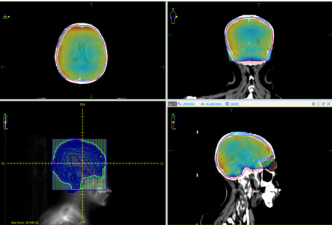

面对郝女士的状况,主任王建华带领放疗科团队迅速投入工作,第一时间为她制定了个体化治疗方案。考虑到郝女士体力衰弱,无法配合常规体位固定,团队启用了西门子GoSim大孔径定位CT。宽大的孔径设计让她在定位时少了诸多不适,有效减少了身体移动带来的误差,而设备捕捉到的高分辨率影像,也为后续靶区勾画和剂量计算提供了清晰可靠的依据。

治疗阶段,医科达VersaHD高端直线加速器正式“登场”。它能灵活塑造照射野,让高剂量射线精准瞄准肿瘤,同时最大程度避开周围正常脑组织,既保证了疗效,又降低了副作用。

更贴心的是,每次治疗前,医院都会通过全程图像引导技术,将实时扫描图像与定位CT比对,校正哪怕微小的体位偏差,确保每一次照射都精准无误。